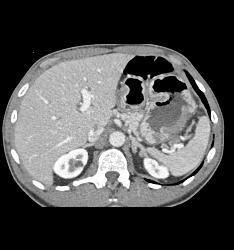

Bulky Tumor C/w Lymphoma Involving Stomach and Kidney